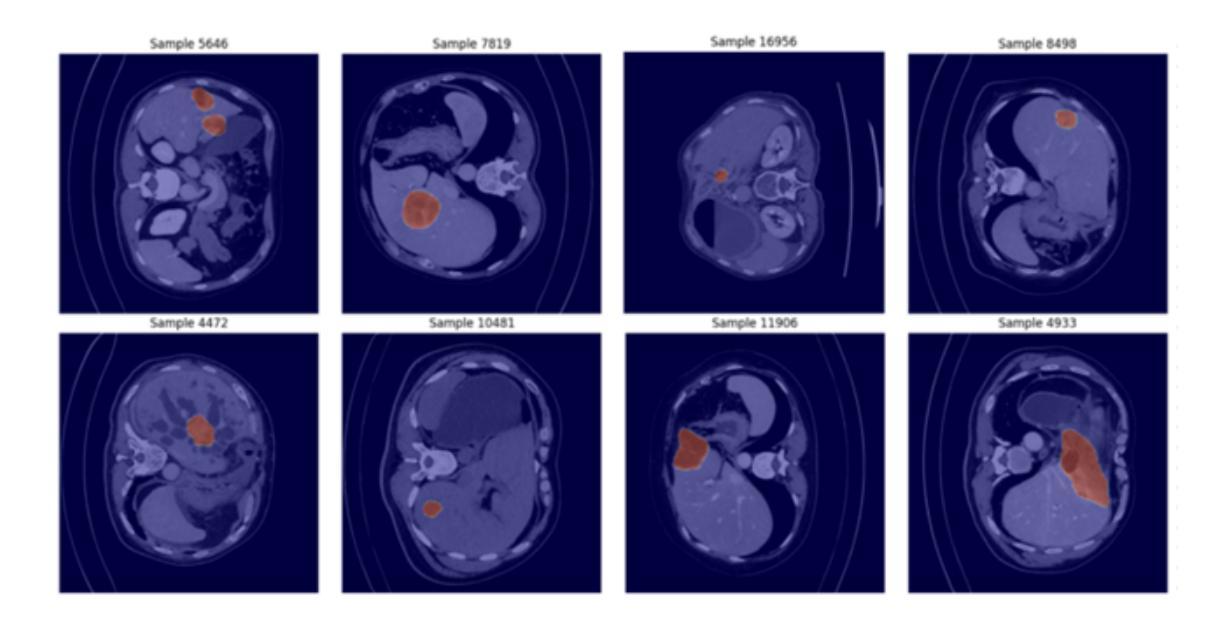

Segmentation of liver structures in multi-phase contrast-enhanced computed tomography (CECT) plays a crucial role in computer-aided diagnosis and treatment planning for liver diseases, including tumor detection. In this study, we investigate the performance of UNet-based architectures for liver tumor segmentation, starting from the original UNet and extending to UNet3+ with various backbone networks. We evaluate ResNet, Transformer-based, and State-space (Mamba) backbones, all initialized with pretrained weights. Surprisingly, despite the advances in modern architecture, ResNet-based models consistently outperform Transformer- and Mamba-based alternatives across multiple evaluation metrics. To further improve segmentation quality, we introduce attention mechanisms into the backbone and observe that incorporating the Convolutional Block Attention Module (CBAM) yields the best performance. ResNetUNet3+ with CBAM module not only produced the best overlap metrics with a Dice score of 0.755 and IoU of 0.662, but also achieved the most precise boundary delineation, evidenced by the lowest HD95 distance of 77.911. The model’s superiority was further cemented by its leading overall accuracy of 0.925 and specificity of 0.926, showcasing its robust capability in accurately identifying both lesion and healthy tissue. To further enhance interpretability, Grad-CAM visualizations were employed to highlight the region’s most influential predictions, providing insights into its decision-making process. These findings demonstrate that classical ResNet architecture, when combined with modern attention modules, remain highly competitive for medical image segmentation tasks, offering a promising direction for liver tumor detection in clinical practice.

在多项对比增强计算机断层扫描(CECT)中,肝脏结构的分割对于肝脏疾病的计算机辅助诊断和治疗计划(包括肿瘤检测)起着至关重要的作用。本研究中,我们调查了基于UNet架构的肝脏肿瘤分割性能,从原始UNet扩展到具有各种骨干网络的UNet3+。我们评估了ResNet、基于Transformer和状态空间(Mamba)的骨干网络,它们都以预训练权重进行初始化。令人惊讶的是,尽管现代架构有所进步,但基于ResNet的模型在多个评估指标上始终优于基于Transformer和Mamba的替代方案。为了进一步提高分割质量,我们将注意力机制引入到骨干网络中,并观察到加入卷积块注意力模块(CBAM)后效果最佳。带有CBAM模块的ResNetUNet3+不仅以Dice得分0.755和IoU得分0.662的最佳重叠指标产生了最精确的边界描绘,而且实现了最低的HD95距离77.911。该模型的总体准确率达到了0.925和特异性为0.926,展示了其在准确识别病变组织和健康组织方面的稳健能力,进一步证明了其优越性。为了增强可解释性,采用了Grad-CAM可视化来突出显示预测区域中最具影响力的部分,从而深入了解其决策过程。这些研究结果表明,经典的ResNet架构与现代注意力模块相结合时,在医学图像分割任务中仍具有竞争力,为临床实践中肝脏肿瘤检测提供了有前景的方向。

本研究探讨了基于UNet架构的肝脏肿瘤分割性能,从原始UNet到UNet3+,并使用了多种骨干网络,包括ResNet、基于Transformer和Mamba的骨干网络。研究意外地发现,ResNet模型在多指标评估中持续优于其他模型。引入注意力机制后,配备CBAM模块的ResNetUNet3+表现最佳,具有最高的Dice得分和IoU,最精确的边界描绘,以及最高的总体准确率和特异性。研究还利用Grad-CAM可视化增强了模型的解释性。结果表明,结合经典ResNet架构和现代注意力模块的方法在医学图像分割任务中仍极具竞争力,为临床实践中肝脏肿瘤检测提供了有希望的方向。